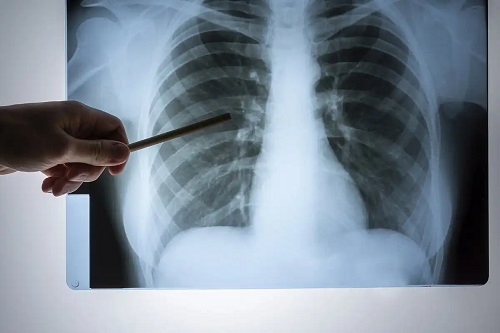

Durerea toracică este un simptom frecvent, care copleșește pacientul. Deși poate fi cauzată de multiple patologii, este important să se țină cont de caracteristicile sale, precum și de localizare. În acest articol, ne vom concentra pe durerea în partea dreaptă a pieptului.

Durerea în partea dreaptă a pieptului: cauze respiratorii

În această secțiune, vom acoperi câteva afecțiuni ale pleurei care sunt capabile să declanșeze durere în partea dreaptă a toracelui. Pleura este o structură formată din două straturi: visceral și parietal. În cel din urmă se găsește inervația necesară transmiterii durerii.

Pneumonie pe partea dreaptă

Infecția țesutului pulmonar înseamnă pneumonie. Este o boală gravă care necesită evaluare medicală imediată. Simptomele includ următoarele:

Dacă procesul infecțios este localizat în plămânul drept, durerea poate apărea pe acea parte a pieptului. Examinarea fizică amănunțită și testele complementare sunt necesare pentru a stabili un tratament eficient timp util.

Pneumotorax pe partea dreaptă

Prezența aerului între straturile pleurei este cunoscută sub numele de pneumotorax. Deși traumatismele o pot provoca, alte cauze posibile includ anumite proceduri medicale și chiar ruptura spontana a unei zone fragile din pleură.

În cazul pneumotoraxului, apar dureri bruște pe partea afectată și dificultăți de respirație. Tratamentul depinde de severitatea tabloului clinic.

Procese tumorale

Tumorile localizate în plămânul drept sunt o altă cauză a durerii în piept. Atunci când procesele sunt localizate în țesutul pulmonar, sunt asimptomatice în stadiile inițiale, deoarece nu implică pleura parietală.

La acești pacienți trebuie urmăriți anumiți parametri: pierderea în greutate, consumul de tutun și expunerea cronică la azbest și fum de biomasă. Pe lângă durere, tusea și dificultățile de respirație sunt frecvente.